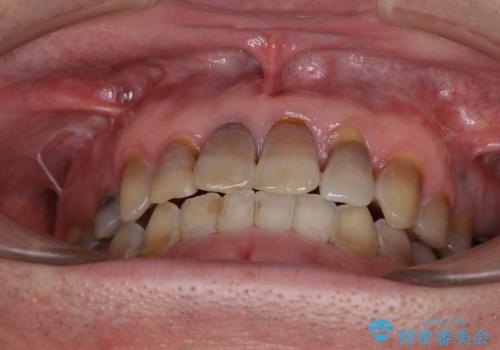

上顎の狭窄歯列 インビザラインによる拡大矯正

- 前歯の叢生と臼歯のクロスバイトを気にして来院された患者様です。

急速拡大装置による上顎の側方拡大を行い、その後はインビザラインより歯列を改善することとしました。

20代後半以降の男性は上顎骨の側方拡大処置の成功率が低く、今回も骨を拡大することができませんでした。

しかしながら、歯列を側方に拡大することができ、その後はインビザラインにて叢生を解消することができました。